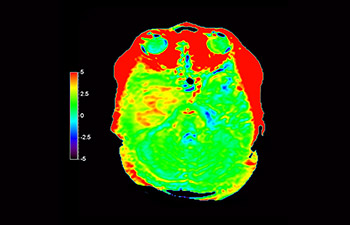

Numa sociedade para a qual os distúrbios neurológicos representam um fardo pesado, a Philips está empenhada em proporcionar uma extraordinária clareza de diagnóstico e orientações de tratamentos para todos os pacientes. Atualmente, embora a RM seja o padrão de excelência no diagnóstico por imagem em neuro-oncologia, sua precisão na classificação de tumores e na avaliação de acompanhamento dos tratamentos pode ser aprimorada. O APT (Amide Proton Transfer) 3D é um método exclusivo de diagnóstico por imagem por RM do cérebro sem contraste que aborda a necessidade de um diagnóstico mais confiante em neuro-oncologia. O APT 3D utiliza a presença de proteínas celulares endógenas para produzir um sinal de RM que se correlaciona diretamente com a proliferação celular, um marcador de atividade tumoral. O APT 3D pode auxiliar profissionais de saúde capacitados na diferenciação entre gliomas de baixo e de alto grau e a diferenciar a progressão tumoral do efeito do tratamento.1

com o APT 3D